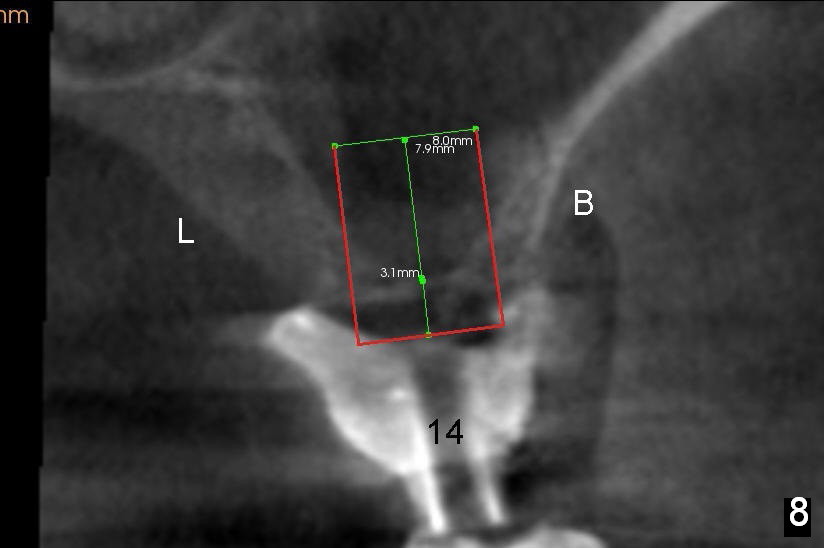

Coronally, a round implant does not appear to obtain more bone contact than a tapered one of the same diameter (Fig.8,10). Internal sinus lift works for this case?